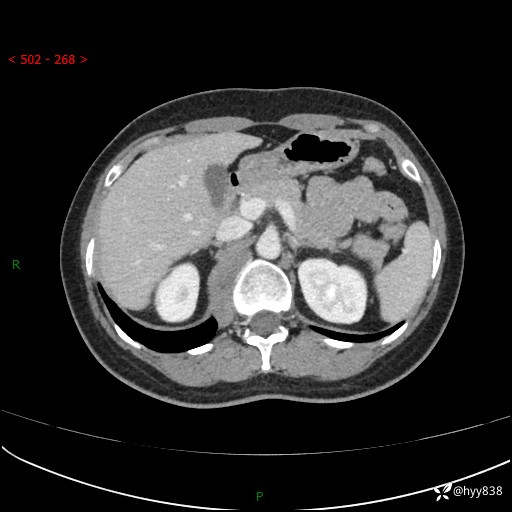

现在都流行跨界,病变也不例外,从腹膜后长到胸腔了---结果公布~

主诉:体检发现右侧腹膜后肿物1天

简要病史:患者于1天前因体检发现右旁肾占位,无肉眼血尿,无畏寒发热,无咳嗽咳痰,无腰腹部疼痛不适,无尿频尿急症状,起病来,患者未行特殊治疗,为求进一步诊治,门诊以"右侧腹膜后肿物"收治入院。 发病来患者精神、饮食、睡眠良好,小便如上,大便正常,体重无明显变化。

临床诊断:腹膜后肿物

上腹部CT增强(动脉期+实质期)(外院平扫)